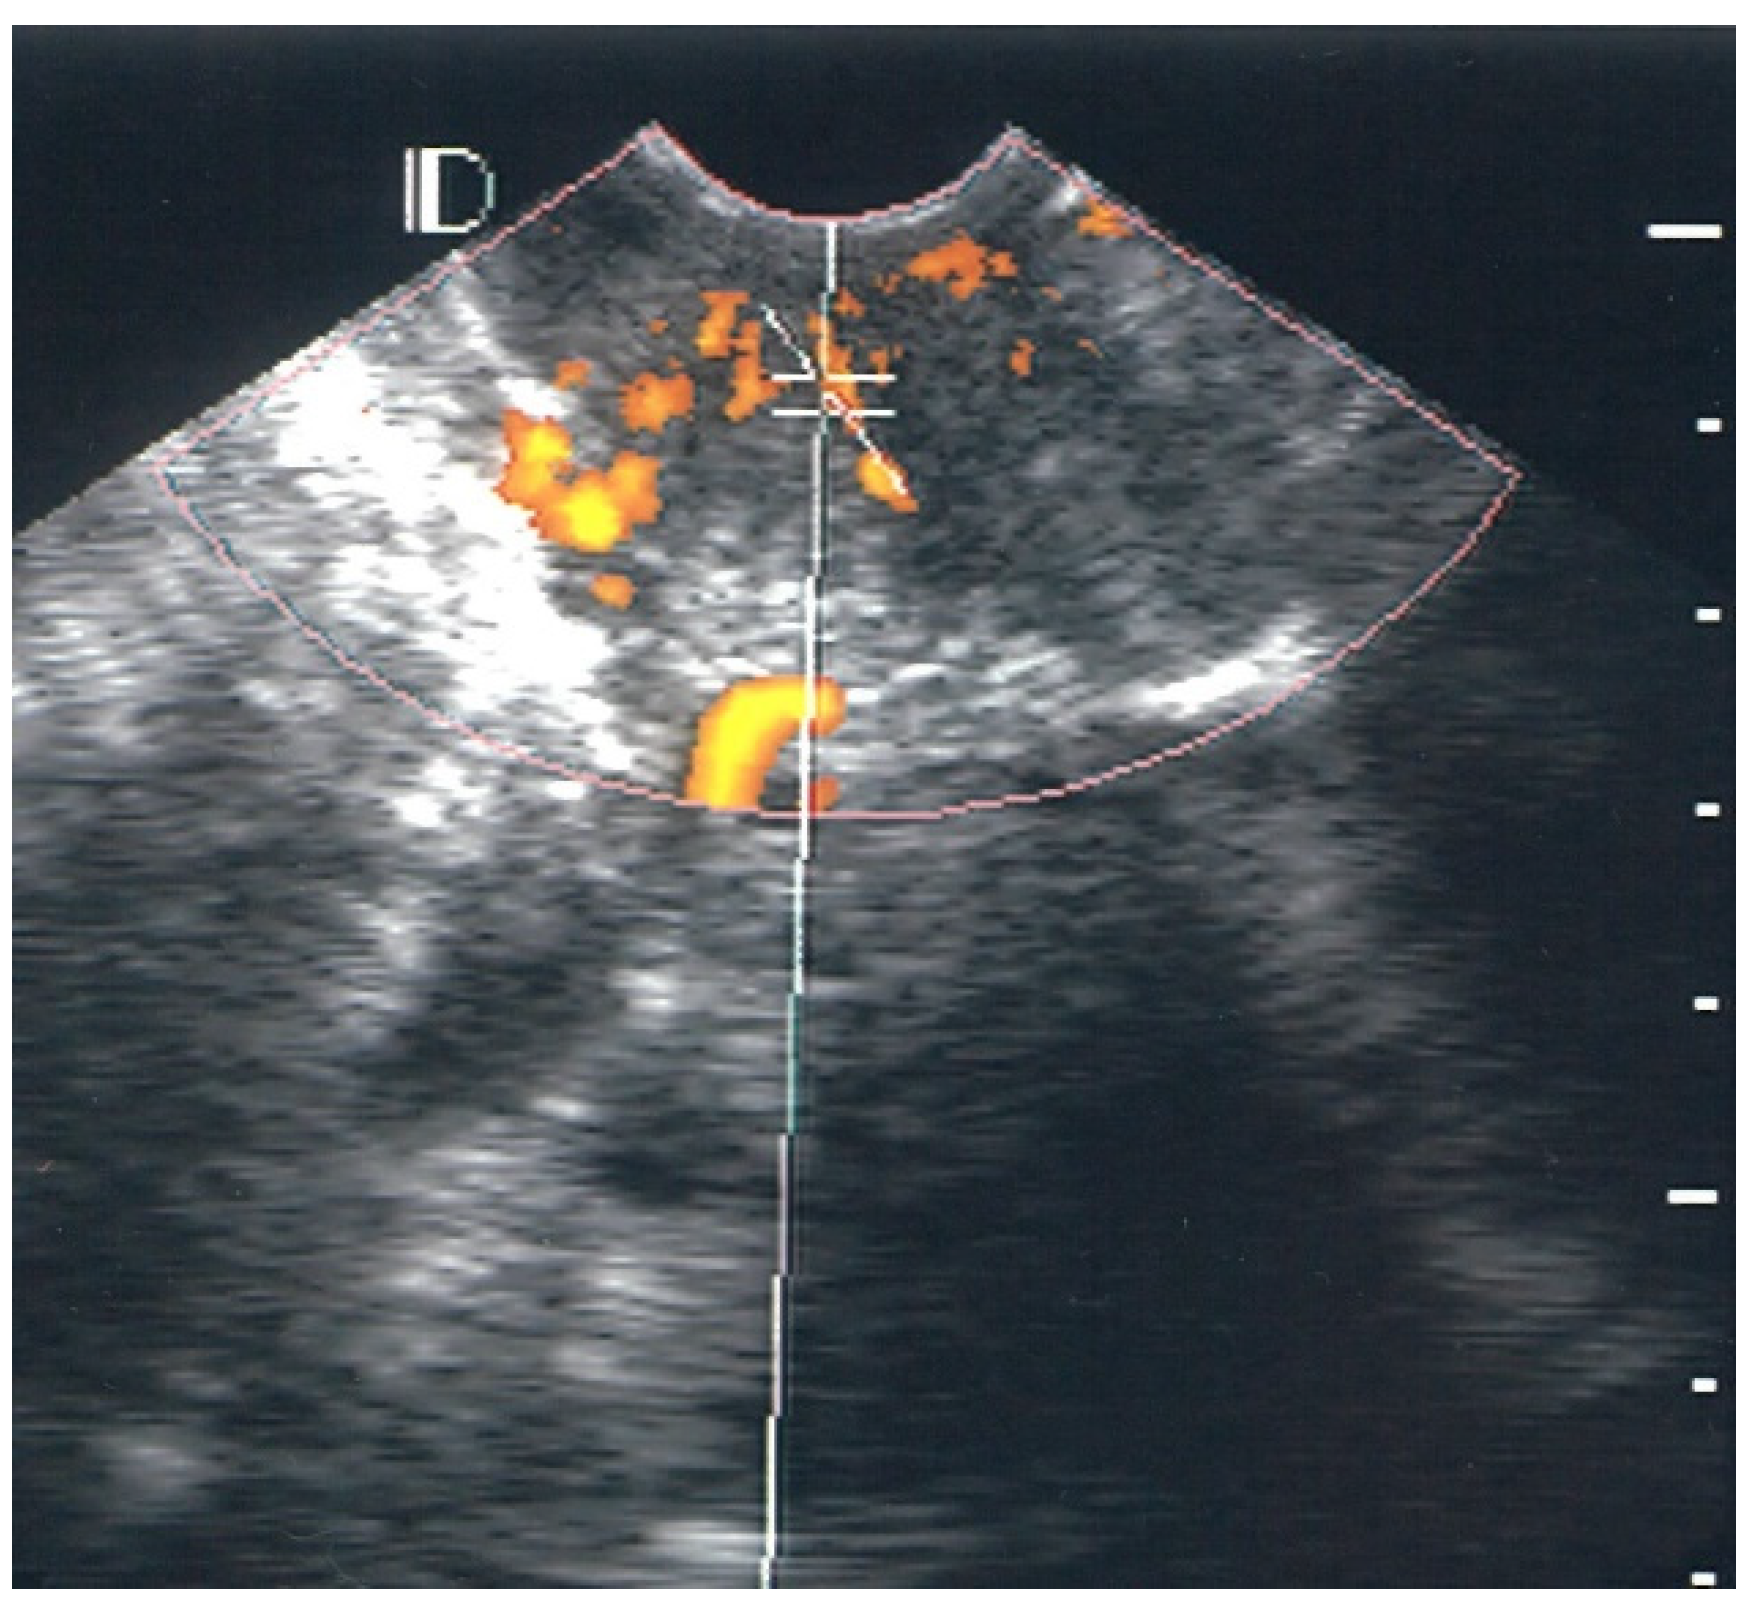

3.1. Visual Classification of Vascularity Findings on TV-PDU

| LSIL | 26 | 0 | 18 | 7 | 1 |

| HPV condyloma | 13 | 0 | 12 | 1 | 0 |

| Normal | 40 | 29 | 10 | 1 | 0 |

| Classification | Numbers of Visualize Vascular Hotspots within Cervix (One Spot: 1 × 1 mm) |

|---|---|

| Class 0 | 0 |

| Class I | 1 to 5 |

| Class II | 5 to 10 |

| Class III | >10 |